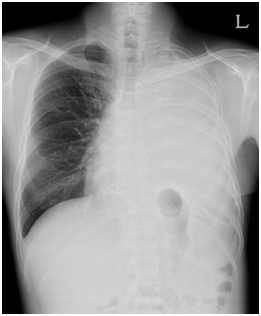

![]() [흉막외 전폐절제술을 시행 받은 환자의 흉부 방사선 사진] |

* 흉막외 전폐절제술을 시행 받은 환자의 흉부 방사선 사진 : 좌측 흉막외 전폐절제술을 시행 받아 좌측 폐가 없음.